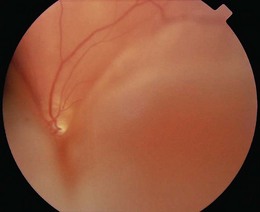

Flashes and floaters are caused by vitreous degeneration, especially in those >65 years and in myopia (short sight). As the vitreous degenerates, the gel liquefies and fluid escapes through perforations in the outer surface of the vitreous overlying the macula. The fluid peels the vitreous off the retina and the remaining contents swirl about on eye movement. The vitreous is attached to the retina in places, and as it detaches, retinal traction may produce flashes and lead to retinal tears. Retinal tears allow fluid from the vitreous cavity to enter the potential space between the retina and the retinal pigment epithelium, causing retinal detachment (Fig. 12.11). The patient notices visual loss starting peripherally and moving centrally.

Microaneurysms, dot and blot haemorrhages, intraretinal microvascular anomalies and venous beading are all surrogate markers for capillary occlusion. If sufficient capillaries occlude, then new vessels will form in the potential space between the retina and the posterior vitreous surface. They differ from normal retinal vessels because they form returning loops that are distally more dilated than their proximal origins. New vessels grow into the posterior surface of the vitreous and are found at the border of perfused and non-perfused retina (Fig. 12.32). The vitreous is most strongly attached to the optic disc, and new vessels here are more likely to haemorrhage than elsewhere.

Fig. 12.32 Types of optic fundal haemorrhage, according to the retinal level.

RPE, retinal pigment epithelium.